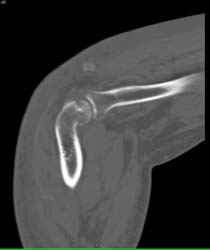

Gout